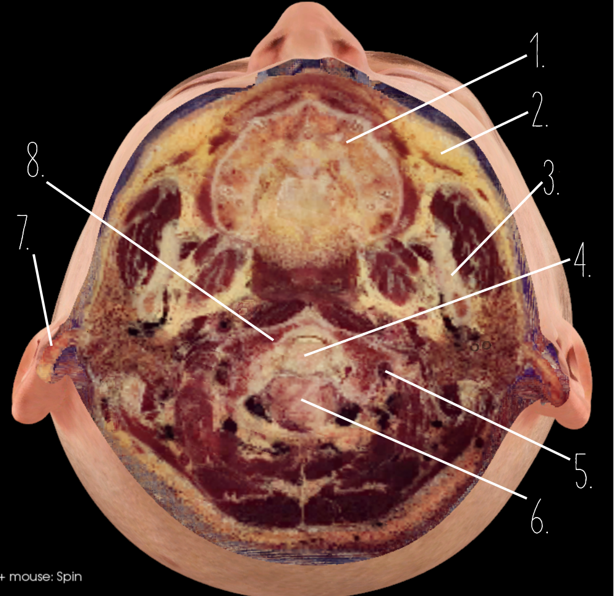

1?

Nasal Bone

2?

Maxillary Sinus

3?

External Acoustic Meatus

4?

Pons

5?

Cerebellum

6?

Mastoid Air Cells

7?

Mandibular Condyles

8?

Sphenoid Bone

9?

Maxillary Bone